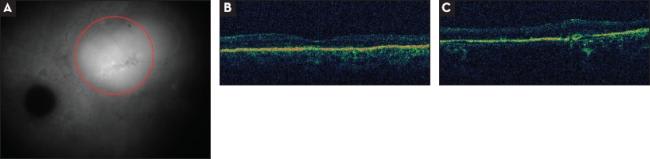

Figure 6. (A) Reduced-fluence PDT with verteporfin was applied to the area of choroidal leakage as shown by the red circle. (B) Ten weeks after treatment the OCT through the central macula shows total resolution of subretinal fluid. (C) The OCT scan through the superior macula shows almost total resolution of the large PED and complete absence of subretinal fluid. Visual acuity is 20/50.

In patients who are "nonresponders," where there is fluorescein angiographic evidence of widespread leakage, particularly where there is a relative paucity of drusen and in which the patchy areas of RPE irregularity may be noted in both eyes, it is recommended that patients undergo indocyanine green angiography to look for areas of choroidal hyperpermeability, both in the affected eye as well as in the fellow eye.8,9 In addition, recent work on enhanced depth imaging with SD-OCT systems has shown that patients with CSC have a thickened choroid, which can help in diagnosing this condition.10 With respect to management, although there are no large-scale randomized clinical trials for this condition, numerous papers have indicated the utility of photodynamic therapy with verteporfin (Visudyne, Novartis), targeting the areas of hyperpermeability noted on the ICG angio gram, as a means to control the exudative process (Figures 4-6).11,12 RPE damage and cystoid macular degeneration often limit the final visual outcome.